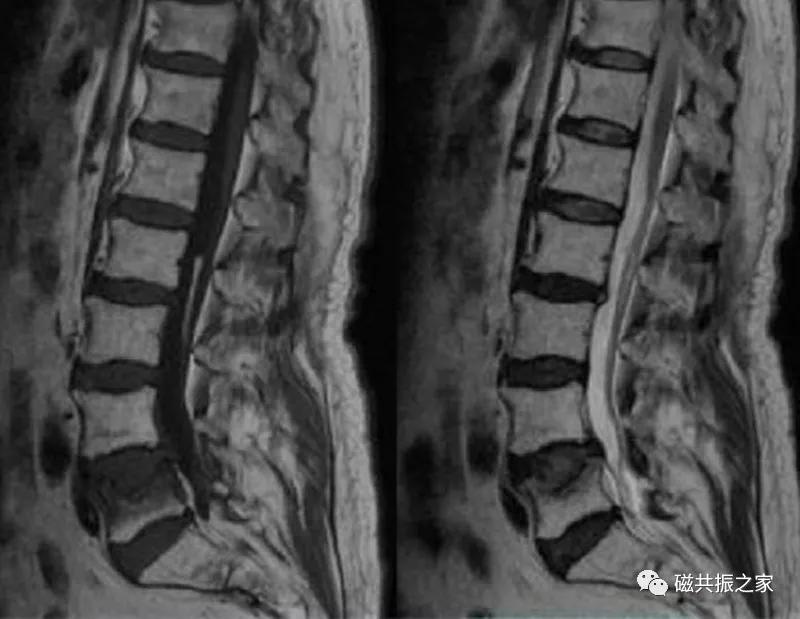

8.椎体骨折

椎体压缩性骨折常成前窄后宽的楔形改变,新鲜骨折(红箭头)常在T1WI呈低信号(出血时可呈高信号),T2WI呈低、中信号,在脂肪抑制的T2WI上呈高信号。椎体陈旧性骨折(白箭头)信号类似于正常椎体信号。如需了解脊柱骨折分型请查阅脊柱骨折的分型。